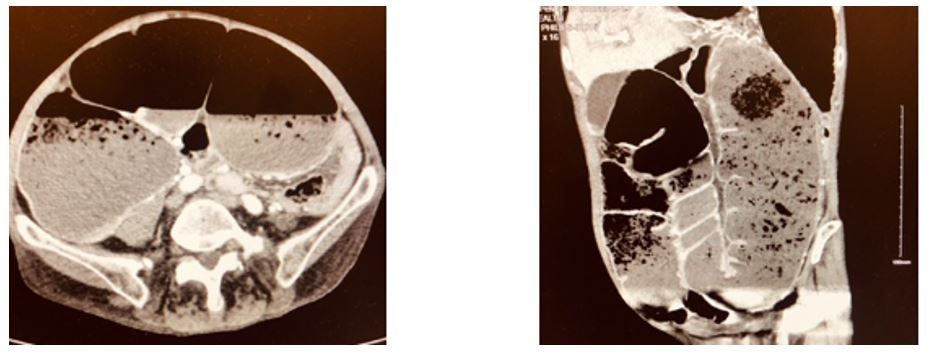

Constipation, bloating, and abdominal pain worsening over 1 week bring a woman in her mid-70s to the ED. Labs are normal. What do you see on the CT scan?

History of present illness. A woman in her mid-70s with a history of chronic back pain and presents to the hospital with constipation, bloating, and abdominal pain that has gradually worsened over the past week. She denies any fever or vomiting. The pain is generalized, radiates to the chest, and comes in waves. Currently she is prescribed opioids and quetiapine.

Vital signs & physical examination. Vital signs are normal. Physical exam is also normal except for a tympanitic distended abdomen in an otherwise very thin woman.

Imaging: See CT